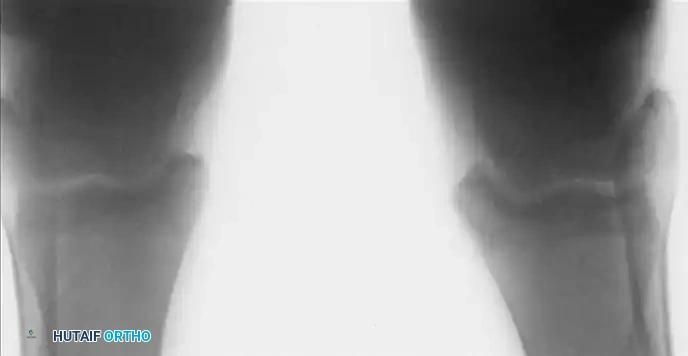

Osteochondral Lesions of the Talus (OCD)

Osteochondral lesions of the talus (OLT), historically termed osteochondritis dissecans by König in 1888 and later applied to the ankle by Kappis in 1922, represent a localized injury to the articular cartilage and underlying subchondral bone.

Etiology and Biomechanics

The vast majority of OLTs are traumatic in origin, typically resulting from severe inversion injuries.

* Anterolateral Lesions: Caused by inversion and dorsiflexion. The talar dome impacts the fibula, creating a shallow, wafer-shaped shear fracture. These are almost exclusively traumatic and are more likely to become symptomatic and displaced.

* Posteromedial Lesions: Caused by inversion and plantarflexion. The talar dome impacts the tibial plafond, creating a deep, cup-shaped compression fracture. These can be asymptomatic for years and may have a genetic or ischemic component.

Imaging and Classification

While the Berndt and Harty radiographic classification (Stages I-IV) is historically significant, MRI is the current gold standard for evaluating the size, depth, and stability of the cartilage cap, as well as the presence of subchondral cysts.